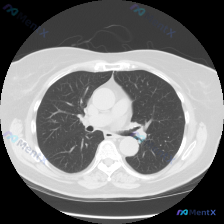

刚整理完一份很有参考意义的胸部CT读片病例,跟大家分享一下,整个分析思路挺值得梳理的。 一、病例影像基本信息 这是一张胸部CT肺窗横断面影像,问题是检出了「Airspace opacity(气腔不透明度)」,完整影像评估结果如下: 1. 胸廓对称,纵隔居中,双侧胸膜无明显积液积气,胸膜光滑 2. 右...

看到一个胸部CT肺窗横断面图像的分析资料,整理了一下思路分享给大家。 首先看病例信息:这是一份胸部CT肺窗图像,主要发现是左肺下叶外侧胸膜下区域有一枚类圆形的实性小结节,边界较清晰,呈实性软组织密度,周围肺组织没有明显的磨玻璃影、卫星灶或胸膜牵拉征象,双肺其余肺野也没有明确的实变、磨玻璃影等异常,胸...

看到一份胸部CT肺窗横断面影像的分析资料,整理一下思路。 病例信息: - 主诉:无具体描述(根据影像分析推测为体检或其他原因发现肺部结节) - 现病史:无明确症状(影像分析未提及) - 关键检查:胸部CT肺窗(横断面) - 影像信息:右肺上叶近肺门/纵隔旁区域可见一类圆形微小结节影,边界相对清晰,密...

看到一个胸部CT肺窗的病例资料,整理了一下分析思路,和大家分享讨论。 先看一下影像的基本信息: - 图像质量清晰,肺窗显示良好,无明显伪影 - 解剖定位在主动脉弓或气管隆突上方,可见双侧肺门血管和气管影 - 左肺上叶可见多发小结节,圆形或类圆形,边缘相对锐利,部分密度较高,主要分布在支气管血管束周围...

看到一个胸部CT肺窗的病例,整理了一下分析思路,和大家讨论。 病例信息: 患者提供的是肺窗胸部CT横断面影像,扫描层面在肺门下方的心室/心房水平。 影像表现: 1. 双肺透亮度基本对称,肺纹理走行自然,无大范围磨玻璃影或实变影。 2. 左肺下叶偏背侧、靠近肺门区域有一个类圆形病灶,直径约5-8mm,...